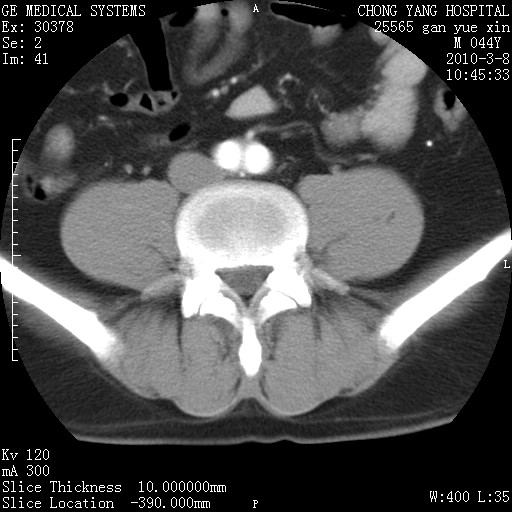

标题: CT24940:主动脉增强,典型病例。 [打印本页]

标题: CT24940:主动脉增强,典型病例。

夹层动脉瘤。

动脉夹层

夹层动脉瘤,典型

主动脉夹层。

动脉夹层的分型:

⒈debakey分型:根据主动脉夹层累及部位,分为三型:ⅰ型:原发破口位于升主动脉或主动脉弓部,夹层累及升主动脉、主动脉弓部、胸主动脉、腹主动脉大部或全部,少数可累及髂动脉。ⅱ型:原发破口位于升主动脉,夹层累及升主动脉,少数可累及部分主动脉弓。ⅲ型:原发破口位于左锁骨下动脉开口远端,根据夹层累及范围又分为ⅲa,ⅲb。ⅲa型:夹层累及胸主动脉。ⅲb型:夹层累及升主动脉、腹主动脉大部或全部。少数可累及髂动脉。

⒉stanford分型:a型:夹层累及升主动脉,无论远端范围如何。b型:夹层累及左锁骨下动脉开口以远的降主动脉。

夹层动脉瘤,少量胸水

夹层动脉瘤;左侧少量胸腔积液。

典型主动脉夹层。